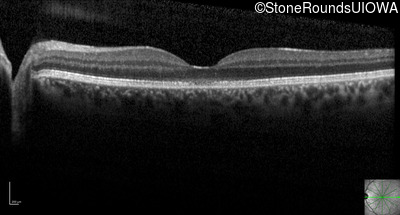

Optical Coherence Tomography - Left - 20/50 +1 sc

Exemplar / OCT Stack

OCT Stack